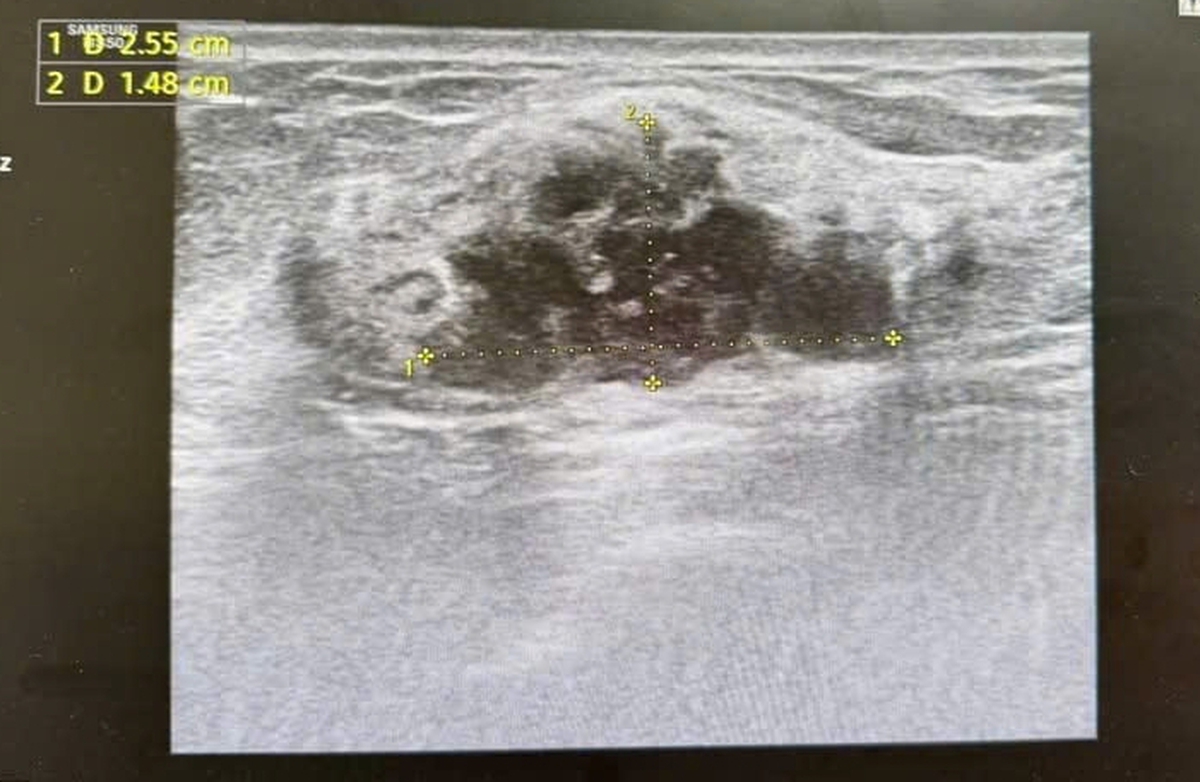

- Năm 2018, bà Lan được chẩn đoán ung thư vú giai đoạn 2, đối diện tuyệt vọng

Năm 2018, bà Lan được chẩn đoán mắc ung thư vú giai đoạn 2. Cú sốc bệnh tật khiến bà suy sụp, tuyệt vọng. "Tôi đã nghĩ mình không còn cơ hội sống" Dân Trí, bà Lan nhớ lại. Nỗi sợ hãi bao trùm, nhưng vì gia đình, bà quyết tâm chiến đấu.